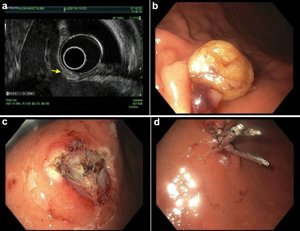

📸interesting case at Geisinger GI by 🌟faculty Dr. Dema Shamoon (Dema Shamoon ): Pt with obstructive jaundice 🌝 → ampullary mass. EUS → FNB 💉: black fluid from specimen. ERCP → Sphincterotomy ✂️exposed a jet-black tumor. Also seen 👀 a Gastric lesion expressing black